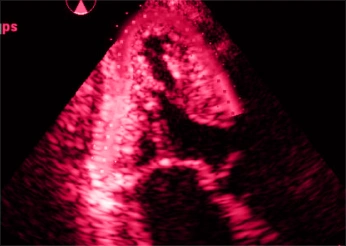

Ecocardiografia 3D

Permitindo análises volumétricas precisas e novas métricas de função.